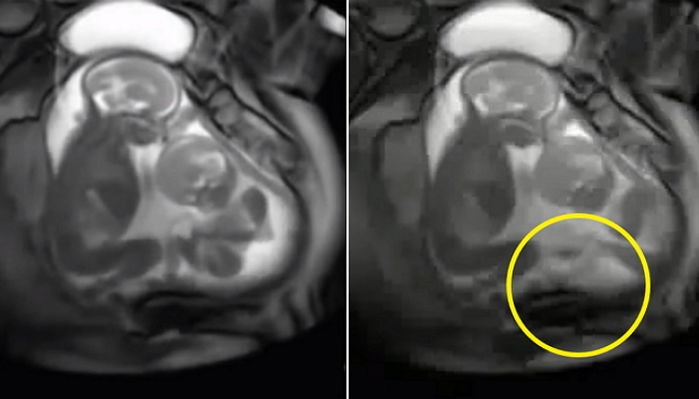

자궁 안에서 서로 주먹질하던 희귀 '단일양막쌍둥이' 극적 출산